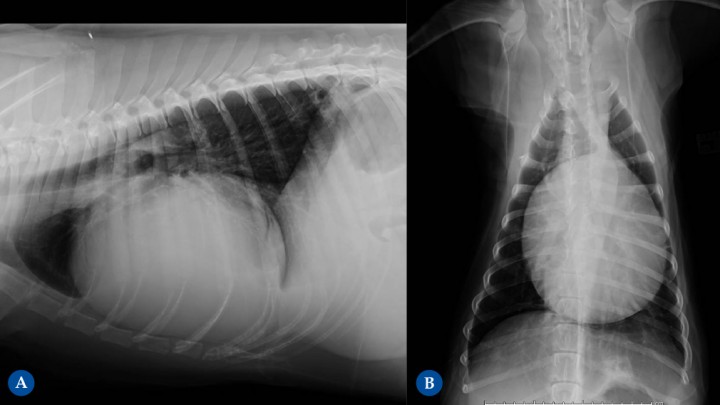

<p>Golden Retriever de 10 años. Hemopericardio y pericarditis reactiva. (<strong>A</strong>) Proyección lateral derecha. (<strong>B</strong>) Proyección ventrodorsal. Diagnosticado previamente de linfoma pericárdico T atípico, en tratamiento quimioterápico. Se puede diferenciar la efusión pericárdica de la cardiomegalia en que la efusión pericárdica ocasiona un engrosamiento globoso generalizado, con bordes lisos, redondeados y muy bien definidos, sin evidenciarse un engrosamiento de una cámara cardíaca en concreto. En esta paciente se observa una silueta cardíaca que ocupa más de 2/3 del ancho de la cavidad torácica en la Fig. 10B y más de un 80% en la Fig. 10A con un mayor eje craneocaudal, ocupando 4 EIC.</p>

Golden Retriever de 10 años. Hemopericardio y pericarditis reactiva. (A) Proyección lateral derecha. (B) Proyección ventrodorsal. Diagnosticado previamente de linfoma pericárdico T atípico, en tratamiento quimioterápico. Se puede diferenciar la efusión pericárdica de la cardiomegalia en que la efusión pericárdica ocasiona un engrosamiento globoso generalizado, con bordes lisos, redondeados y muy bien definidos, sin evidenciarse un engrosamiento de una cámara cardíaca en concreto. En esta paciente se observa una silueta cardíaca que ocupa más de 2/3 del ancho de la cavidad torácica en la Fig. 10B y más de un 80% en la Fig. 10A con un mayor eje craneocaudal, ocupando 4 EIC.